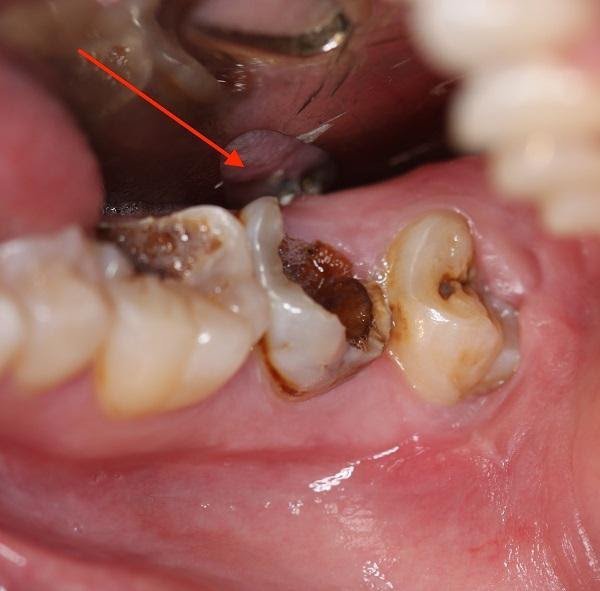

Răng cối sâu vỡ lớn cần nhổ

Khi tiến hành kiểm tra, phát hiệ-n răng gặp một trong các vấn đề sau đây, bác sĩ sẽ chỉ định nhổ răng:- Phần thân và chân răng bị phá hủy nhiều, mất hết các chức năng và không thể điều trị hay tái tạo được nữa.

Phần thân và chân răng bị hư tổn nặng, không thể điều trị cần phải nhổ bỏ